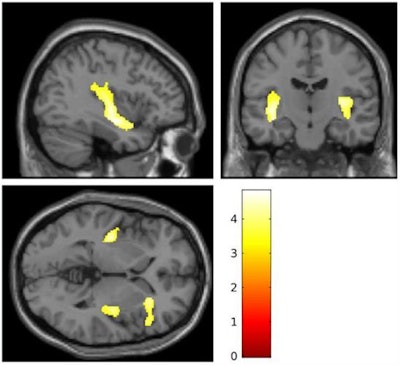

Researchers performed MRI brain scans on 20 teenage girls who had a history of severe self-injury, such as cutting, and 20 girls with no history of self-harm. The scans revealed clear reductions in volume in the insular cortex and inferior frontal gyrus among the 20 self-injuring girls, compared with those in the control group.